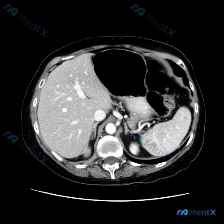

最近看到一份很有意思的影像会诊资料,初始问题是“判断图像中的脾脏病变”,但仔细读片后发现整个方向都偏了——这个病例的思维陷阱非常典型,整理出来和大家分享一下。 先看影像事实(单张腹部增强CT横断面,软组织窗,动脉期/早期门脉期) 1. 被“点名”的脾脏 影像明确描述:脾脏形态大小正常,实质密度均匀,...

今天整理了一个很有意思的读片案例——提问明确指向“脾脏病变的特殊异常”,但看完影像和分析后,发现逻辑焦点其实需要转移。 先放影像核心事实 这是一张腹部横断面增强CT(软组织窗),图像质量良好: - 脾脏:大小、形态完全正常,密度均匀,未见明确占位性病变; - 肝脏:是唯一有阳性发现的器官——肝实质内...